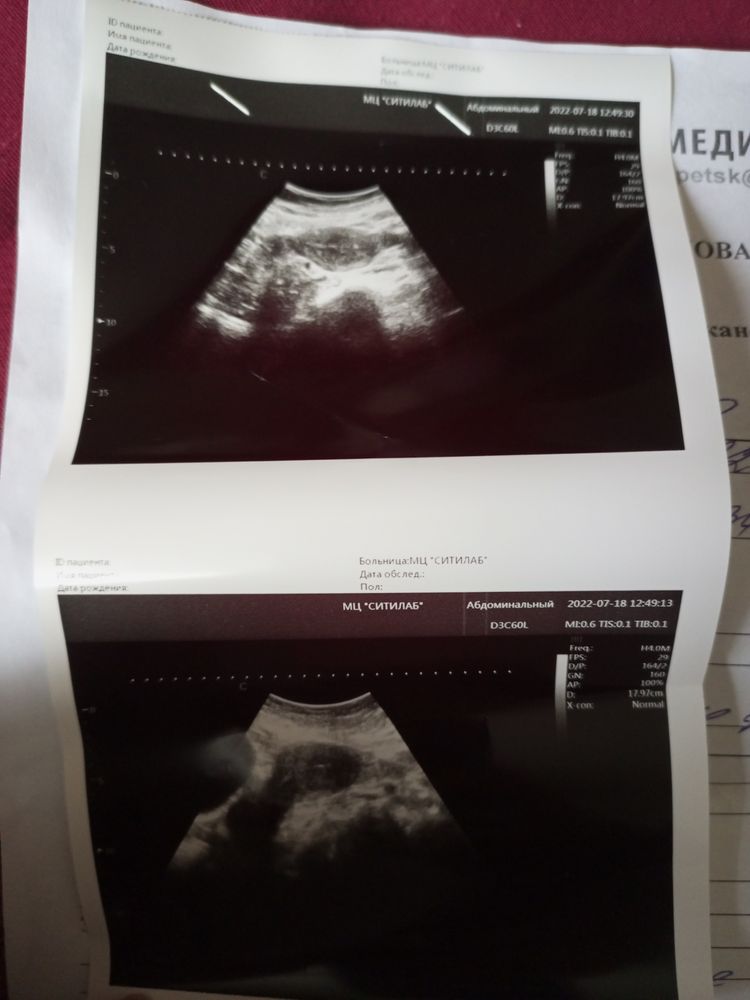

Здравствуйте скажите пожалуйста у меня цикл не равномерный судя по УЗИ с 23 мая и 18 июля разные там матка другая размером в июля половой акт был не защищён Изображение

Точечка - это не там, это артефакт. На снимках - матка в профиль и в ширину. Вы забыли написать в какой день цикла сделали УЗИ. Яоб этом спрашиваю не из любопытства, эндометрий линейный, не имеет толщины. Врач Сикирина О.И.

Сикирина Ольга, УЗИ делала сегодня цикл я вам не могу сказать 1 марта были последний раз дела. У меня тест показывал еле видную вторую полоску. Может врач не увидеть беременности. Эндометрия линейный это что Изображение